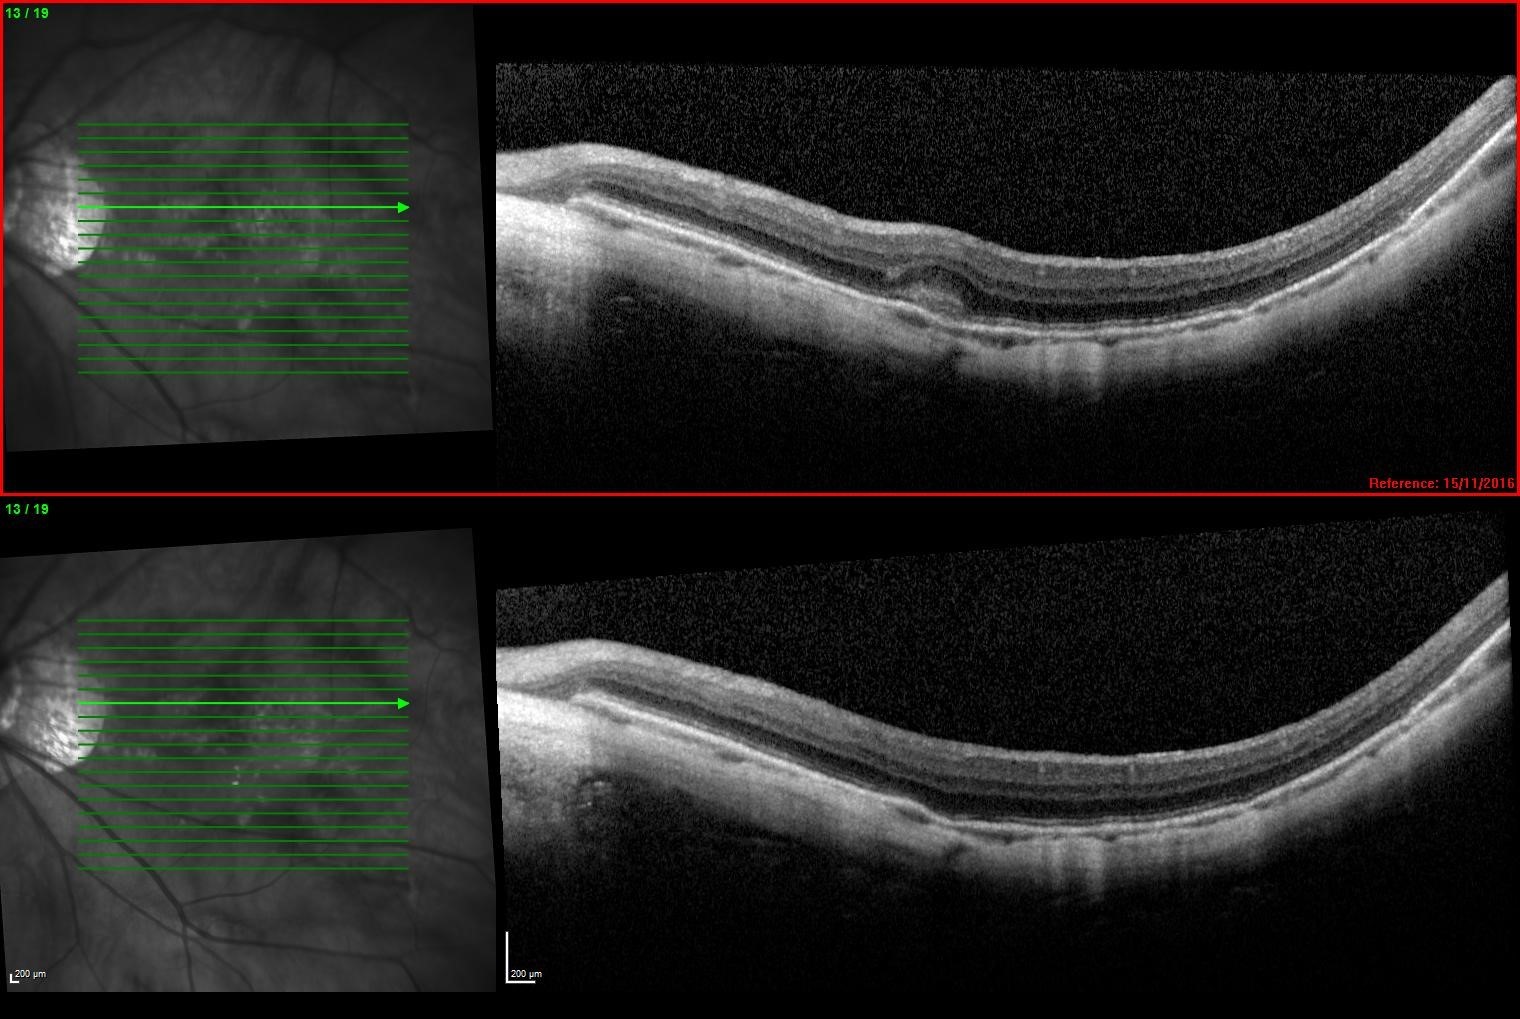

Anterior OCT of the lens showing 160µm of central clearance and well-aligned base curve

OCT of the inferior scleral landing zone showing limbal clearance and well-aligned landing angle

Using the data from the trial fitting process the patient’s first custom lens was designed with 200µm of sagittal difference between meridians and a spherical base curve and power of 7.8mm and -3.50D respectively. On delivery the lens had even scleral alignment and after settling 160µm of central clearance. The lens was quick to align with the ‘flat’ meridian’s marking along 30 degrees, matching the principal meridians of flexure on the over-topography of the trial lens.